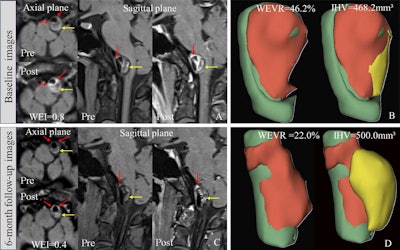

- ‘Dark-light-dark sign’ on MRI predicts rectal cancer metastasisby Will Morton

Absence of the novel tumor feature on contrast-enhanced T1-weighted imaging was associated with a higher risk of lymph node metastasis...